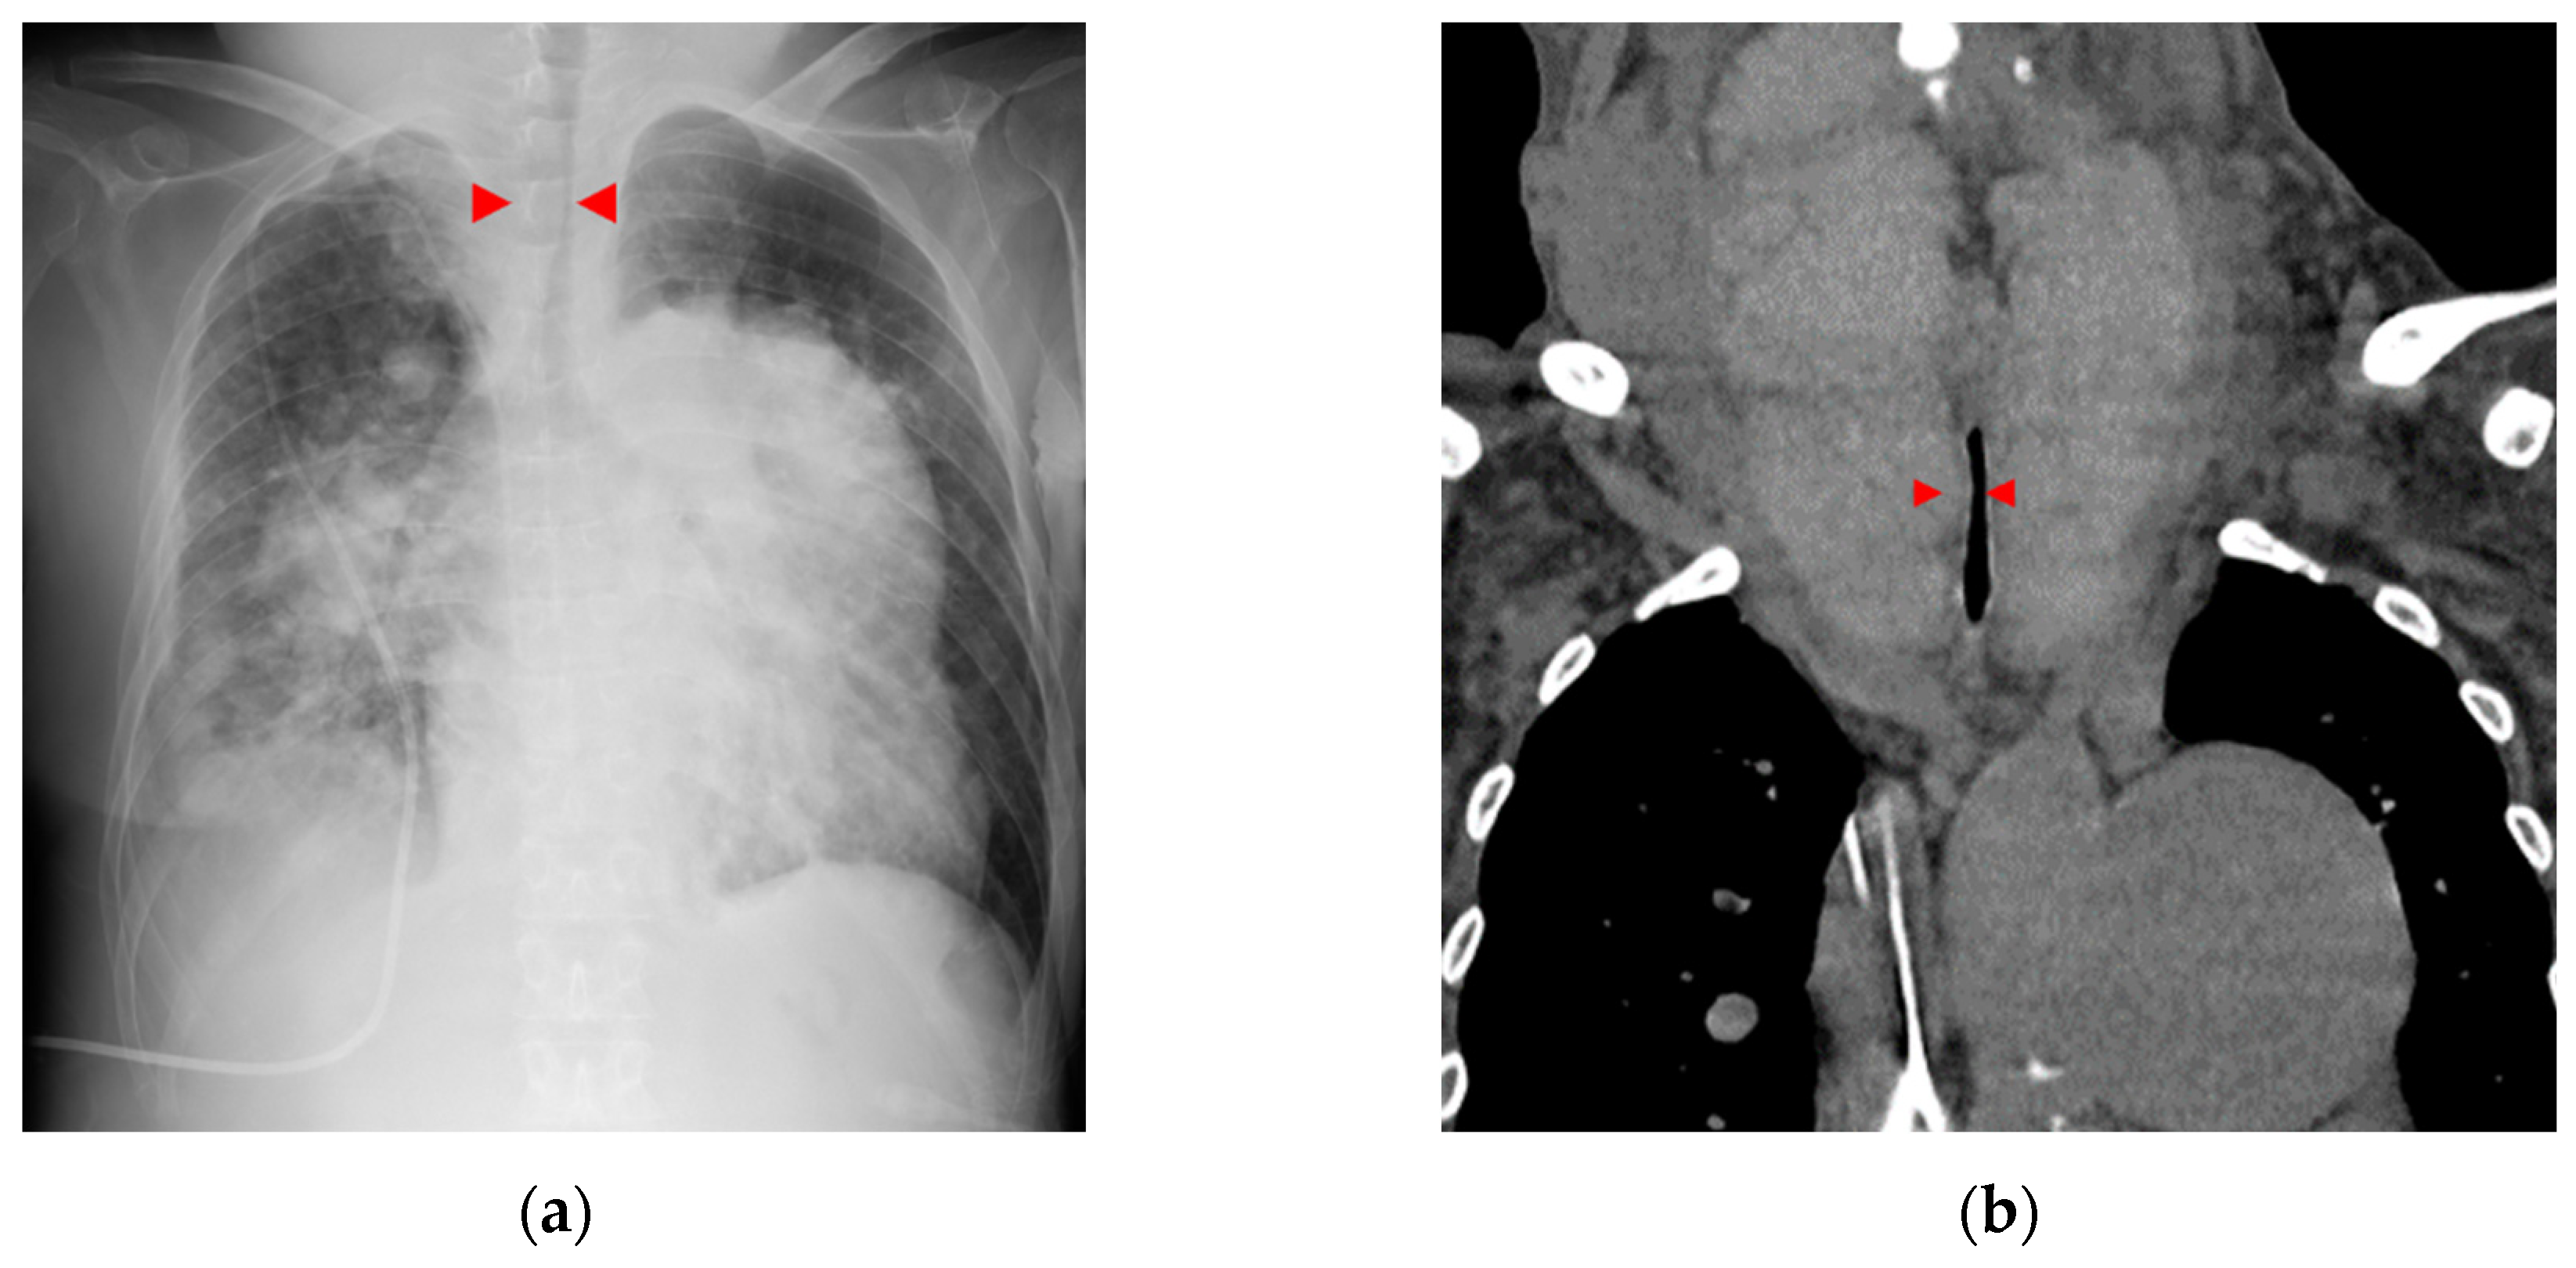

A 34-year-old woman was diagnosed with primary pulmonary hypertension (PPH). At that time, the current IPAH was called PPH. Then she underwent right heart catheterization, and her mean pulmonary artery pressure was 73 mmHg. She complained of dyspnea at rest corresponding to World Health Organization functional class IV. After diagnosing with PPH, she was treated with continuous intravenous epoprostenol. At 37 years of age, she started complaining of neck swelling. Thyroid studies showed Thyroid-stimulating hormone (TSH) = 0.01 μIU/mL (normal range: 0.35-4.94 μIU/mL), Free T3 = 19.88 pg/mL (normal range: 1.71-3.71 pg/mL), Free T4 = 4.86 pg/mL (normal range: 0.70-1.48 pg/mL), thyroid stimulating antibody = 465% (normal range: 0-180%), so she was diagnosed with Grave’s disease and prescribed thiamazole. Epoprostenol at this time was 15 ng/kg/min. Epoprostenol was titrated to decrease mean pulmonary artery pressure in combination with an endothelin receptor antagonist and a phosphodiesterase 5 inhibitor [10]. Epoprostenol maintained at 60-70 ng/kg/min after 14 years of treatment, and mean pulmonary artery pressure decreased to 30-35 mmHg. Thyroid function was controlled by therapy for Grave’s disease using thiamazole and levothyroxine. Nevertheless, her thyroid gland enlargement worsened as epoprostenol was titrated (Figure 1a, b). At 56 years of age, she was admitted to the local hospital due to worsening dyspnea. However, cardiogenic shock and respiratory failure with hypercarbonemia were observed, and she was transferred to our hospital the next day. At admission to our hospital, the patient’s vital signs were blood pressure of 97/62 mmHg, pulse of 117 bpm, and oxygen saturation of 88% with oxygen at 10 L/min through the mask. On examination, the auscultation revealed coarse crackles in her lungs and strider in her neck. Radiography of the chest revealed bilateral pulmonary congestion and airway stenosis (Figure 2a). Computed tomography of the chest also revealed airway stenosis by her giant goiter (Figure 2b). Blood gas analysis on 10 L/min of oxygen showed pH: 7.2, PaO2: 63.7 mmHg, PaCO2: 73.9 mmHg and HCO3-: 28.4 mmol/L, indicating respiratory failure with hypercarbonemia. Thyroid studies showed TSH = 2.265 μIU/mL, Free T3 = 1.52 pg/mL, Free T4 = 0.90 pg/mL. Tracheal intubation was difficult due to severe airway stenosis. Treatment with noninvasive positive pressure ventilation, dobutamine, and noradrenaline was ineffective, and she passed away on the 12th day after admission. Pathological autopsy was performed. Gross thyroid findings included diffuse enlargement (weight 675 g, size 14 cm x 6 cm) and compressive constriction of the upper airway by the thyroid gland (Figure 3). Histological findings of the thyroid gland showed increased thyroid follicle growth and increased colloidal resorption, suggesting a hyperthyroid state (Figure 4). There were no obvious malignant findings. The cause of death was considered to be respiratory failure due to airway narrowing caused by thyroid gland enlargement. The enlarged goiter was thought to be due to continuous intravenous epoprostenol therapy for IPAH.

Figure 1. Computed tomography imaging course of thyroid gland enlargement. The thyroid gland markedly increased. (a)At 45 years of age; (b)At 54 years of age.

Figure 2. Imaging findings on admission. (a) Chest X-ray. Pulmonary congestion, enlargement of the cardiac shadow, and airway stenosis were detected (red arrowhead). (b) Computed tomography.Thyroid gland enlargement was observed. Tracheal compression and stenosis due to goiter (red arrowhead).